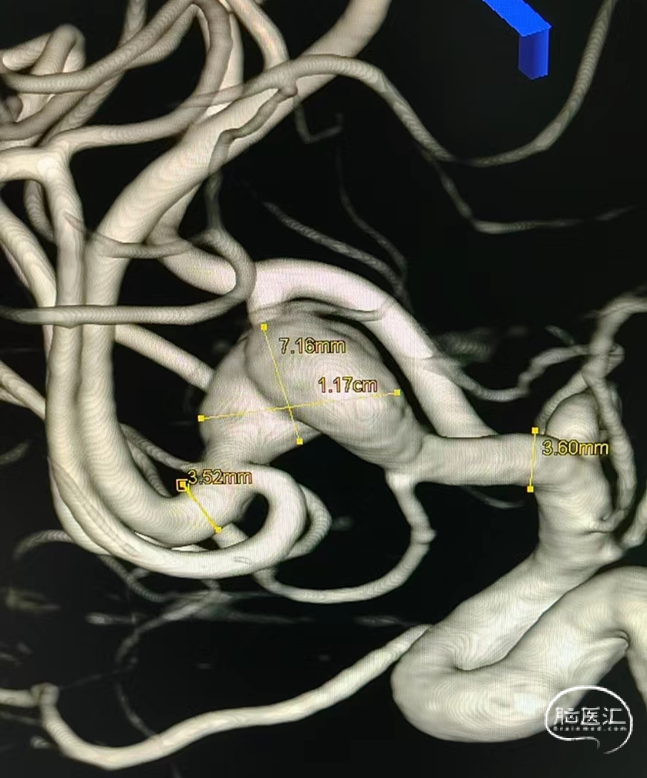

1. 患者L-M1段夹层动脉瘤,约14.0*7.2mm,远端M2段血管管径约3.52mm,近端M1段血管管径约3.6mm。

拟选用4.0*20 Pipeline™ Flex血流导向密网支架,远端铆钉在M2段拐弯以远,近端着陆在M1段起始,如图: